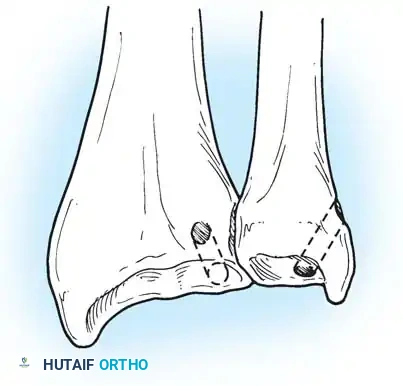

If the DRUJ remains unstable after soft tissue repair, temporary transarticular K-wire fixation may be necessary to protect the repair during the initial healing phase.

Radiographic confirmation of temporary transarticular K-wire fixation stabilizing the DRUJ following complex TFCC repair.